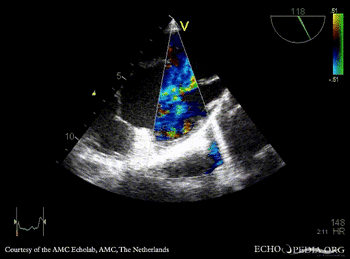

| A5CH: muscular VSD